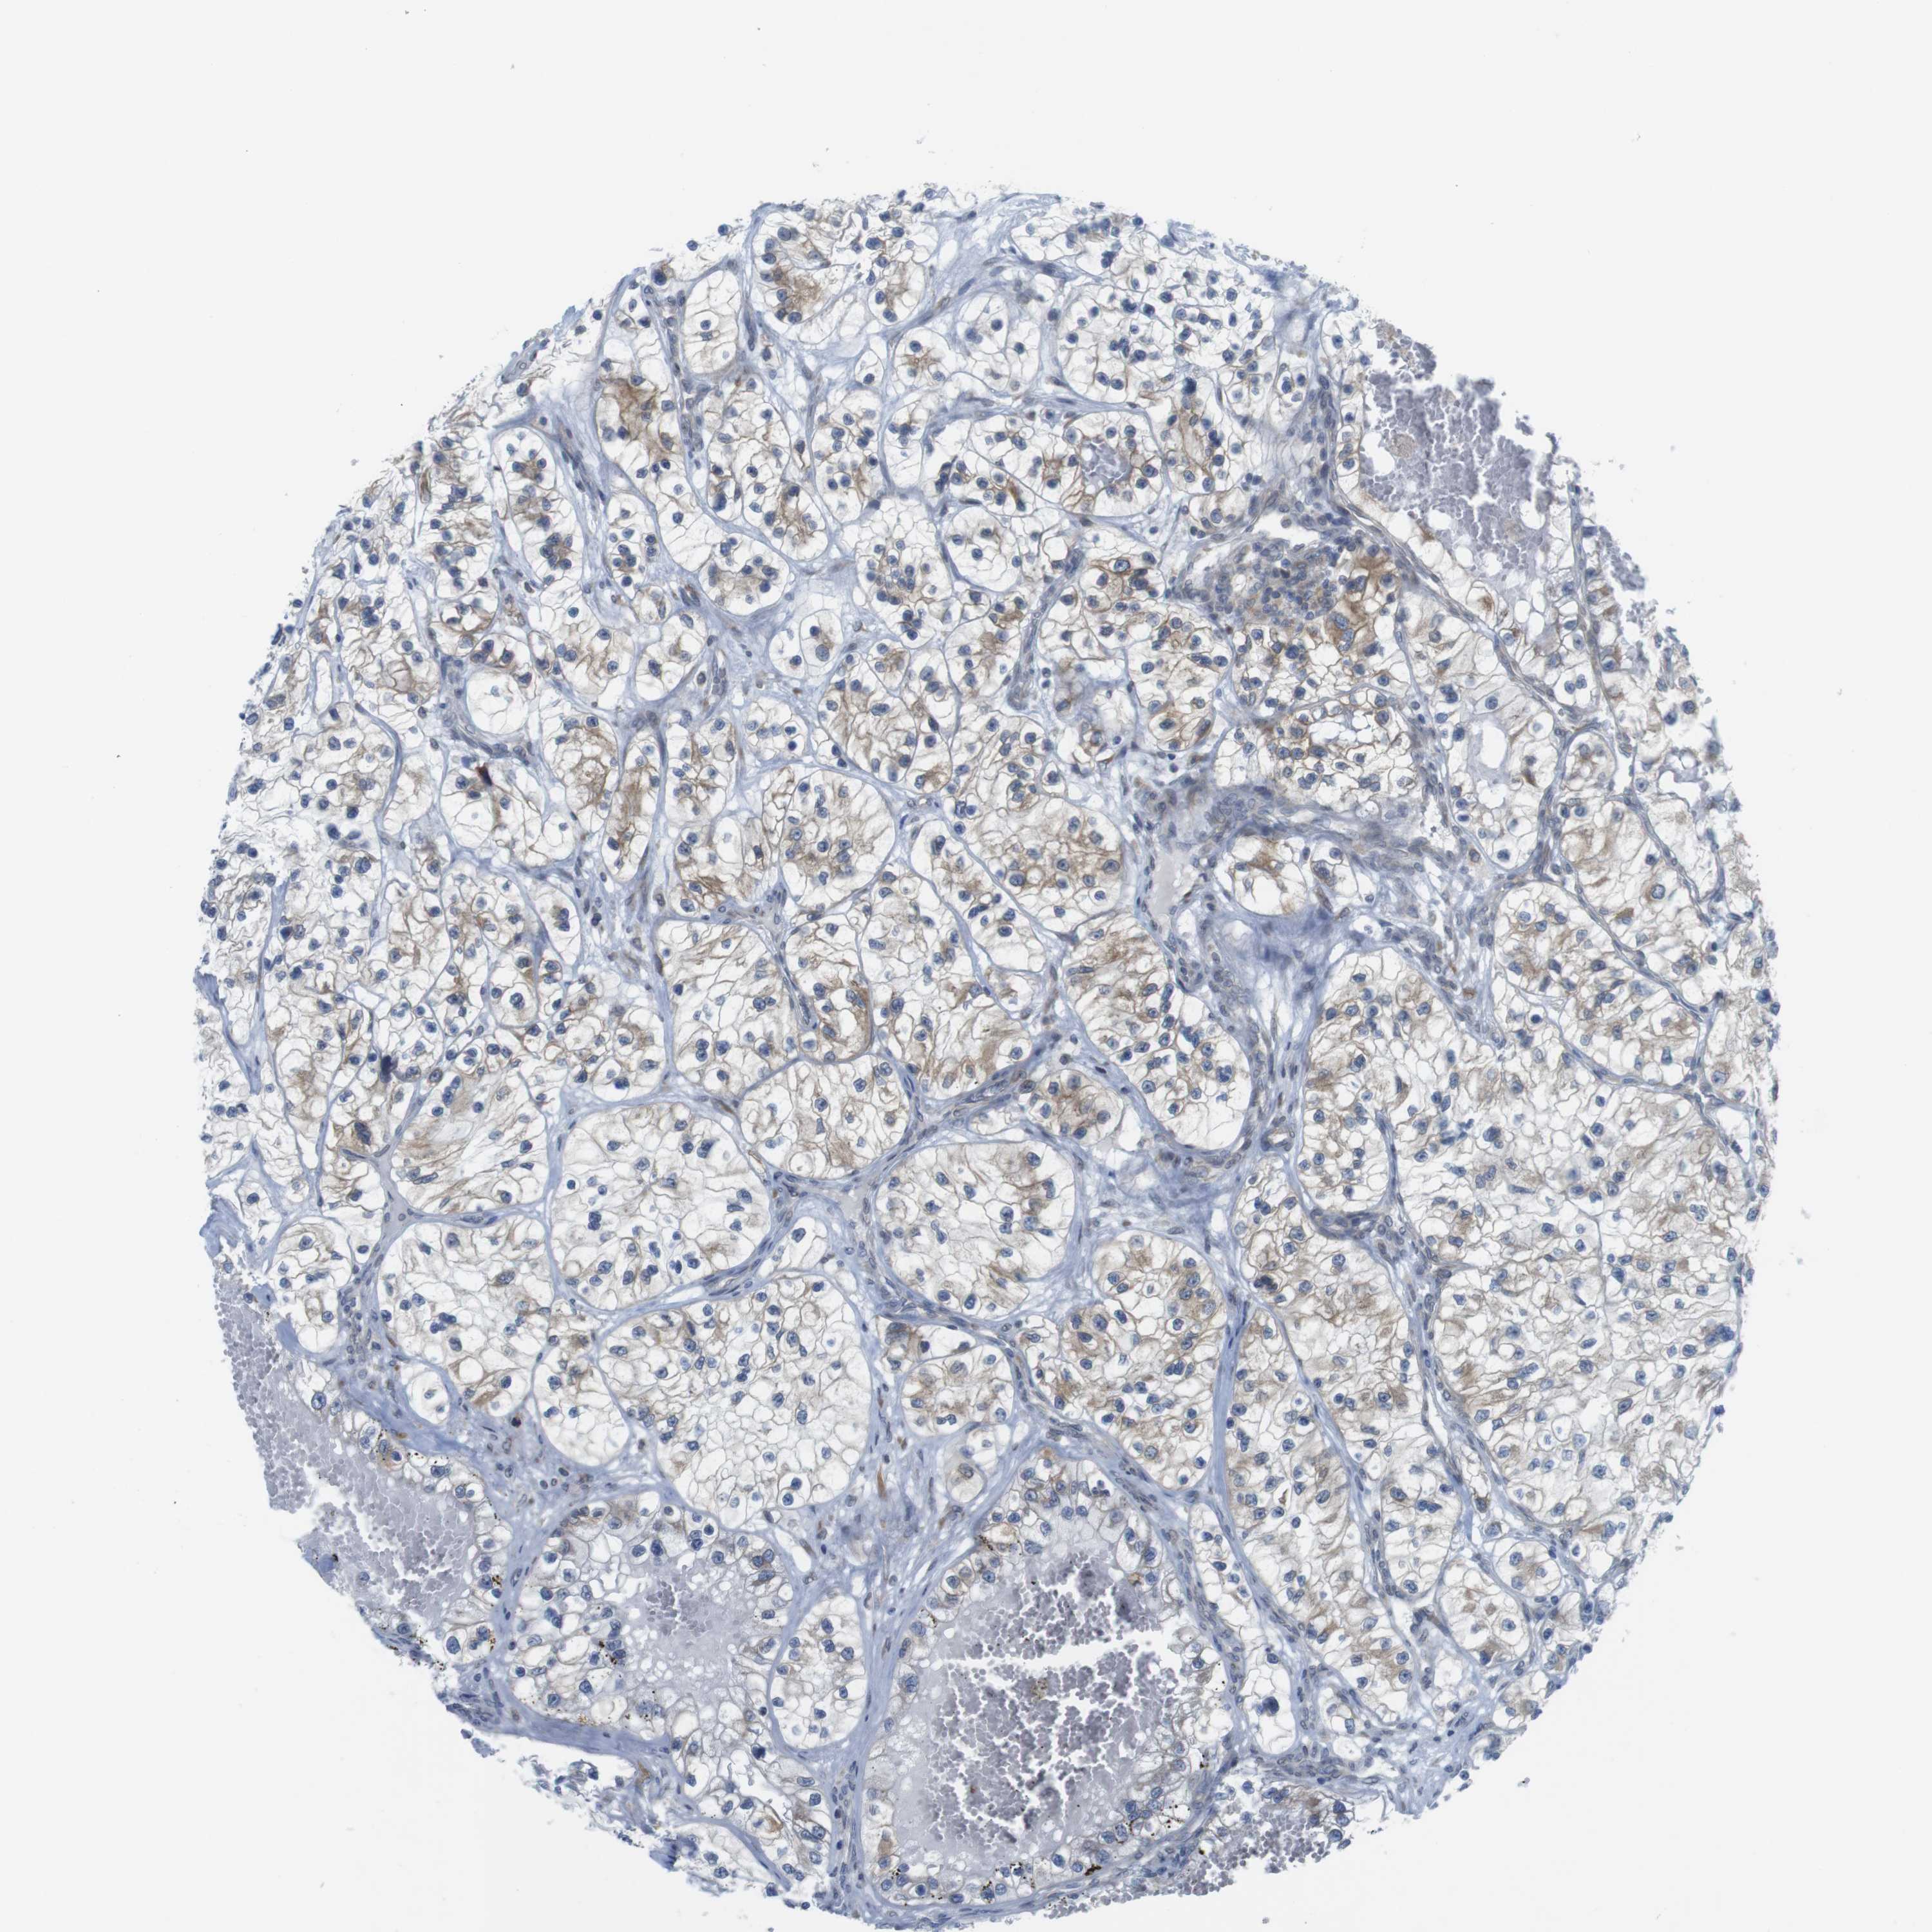

CANCER RENAL CANCER Show tissue menu

KICH TCGA KIRC TCGA KIRC VALIDATION KIRP TCGA PROTEIN RCC CPTAC PROTEIN EXPRESSION